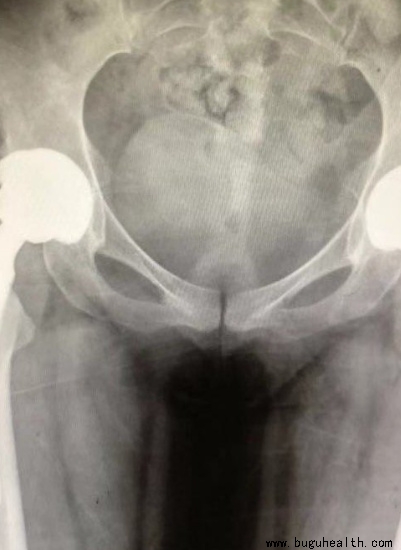

布骨医学科普:中青年早期股骨头坏死的保髋治疗方法!

股骨头坏死(osteonecrosis of the femoral head,ONFH)是关节外科常见且难治的疾病之一,是由多种因素引起股骨头血运异常,进而引起ONFH及塌陷,最终导致髋关节功能严重障碍的疾病。美国每年ONFH新发病例在2万~3万人,主要以20~50岁中青年为主。一项流行病学调查显.....